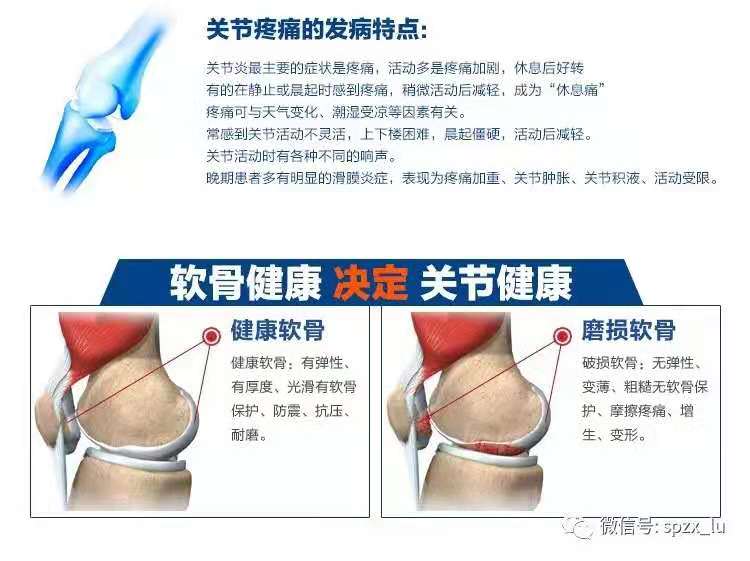

有效改善膝盖炎

硝酸钠氨基匍萄糖缩短促炎性肿瘤细胞成分和一些参与者骨膝盖骨炎的成分 ,具备有抗感染的帮助。[1]

清理损毁软骨

氨基提子糖是环节软骨的注意营养成分,外源性含量氨基提子糖,激起软骨血细胞合成图片核蛋白多糖和胶原仟维,导出软骨基本材料,修复工具工作能力破埙软骨,使环节软骨政治意识修复工具工作能力工作能力增强。[2]